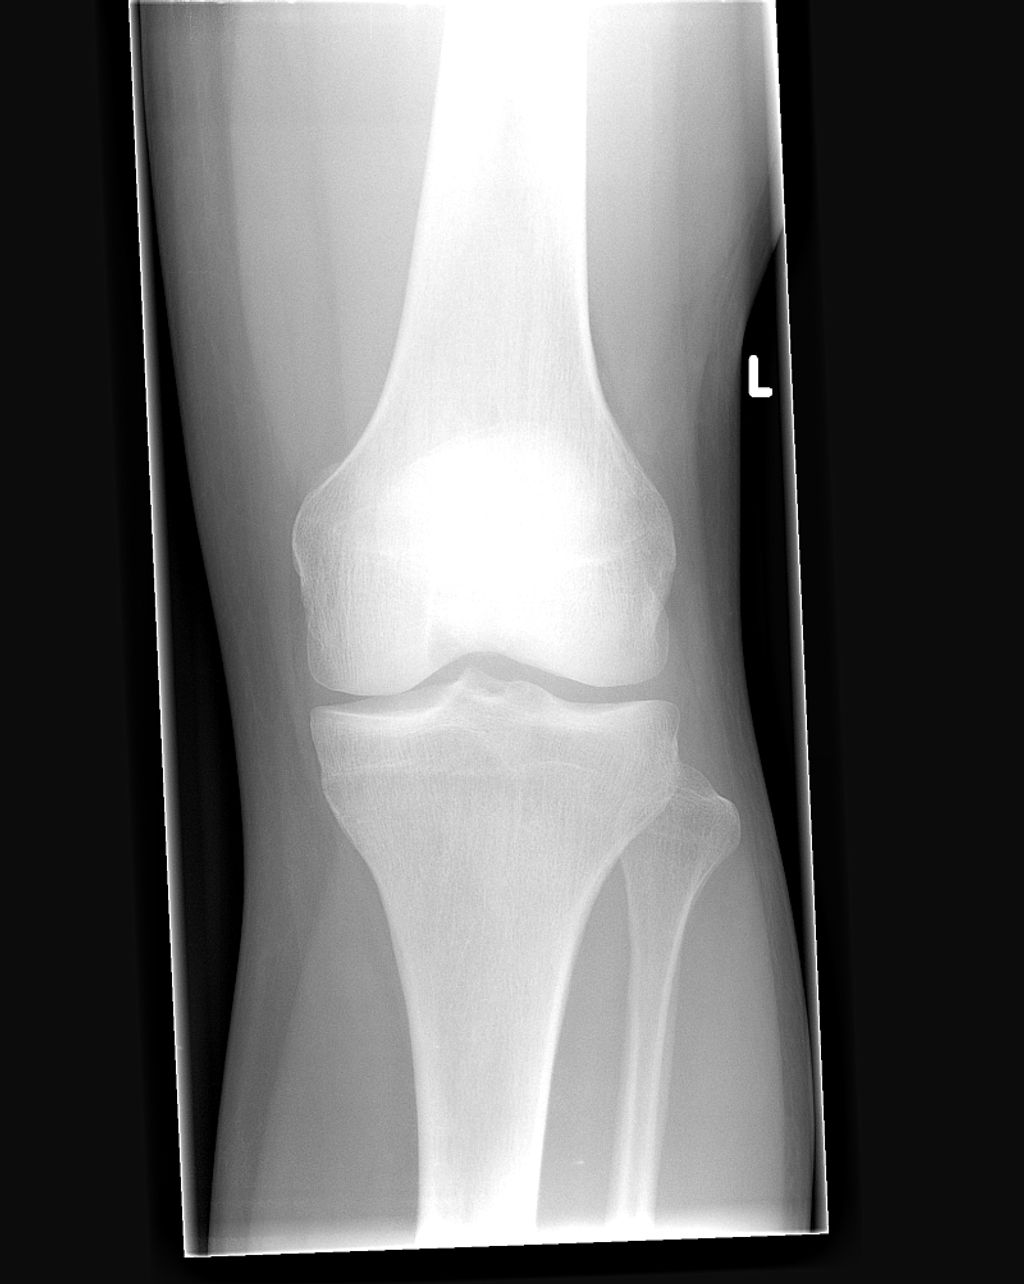

When we suspect inverted knees, we often turn to imaging techniques to confirm the diagnosis. These methods provide us with a detailed view of the knee’s structure, allowing us to assess the extent of inversion and any associated conditions. The most common imaging techniques include X-rays, MRI (Magnetic Resonance Imaging), and CT (Computed Tomography) scans.

- X-rays are typically the first step, offering a clear image of bone alignment and joint space.

- MRI scans provide a more detailed image, showing soft tissues such as ligaments and cartilage.

- CT scans combine X-rays from different angles to create cross-sectional images of the knee, which can be particularly useful in complex cases.

Tip: It’s essential to choose the most appropriate imaging technique based on the individual’s symptoms and physical examination findings to ensure an accurate diagnosis.